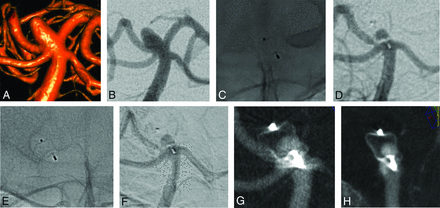

All aneurysms and patients underwent at least 1 VasoCT during the follow-up, showing partial WEB opacification without neck or aneurysm opacification (Fig 2) in 3 patients (patients 2, 5, and 6), complete WEB opacification without neck or aneurysm opacification (Fig 3) in 3 patients (patients 1, 7, and 8), partial WEB opacification and neck opacification (Fig 4) in 1 patient (patient 3), and complete WEB opacification and dome opacification (Fig 5) in 1 patient (patient 4). This last patient was treated with an inappropriately oversized (mean aneurysm width, 6.7 mm, and the implanted device was a WEB 17 SL 7 × 3 mm) WEB device.

3D (A) and 2D (B) DSA show a basilar artery aneurysm. Nonsubtraction (C) and subtraction (D) images of the first DSA follow-up after 1 year show partial filling of the WEB with contrast. A similar finding is observed at 2 years (E and F). VasoCT in 2 different views (G and H) confirms a partial opacification of the WEB and no opacification of the aneurysm.